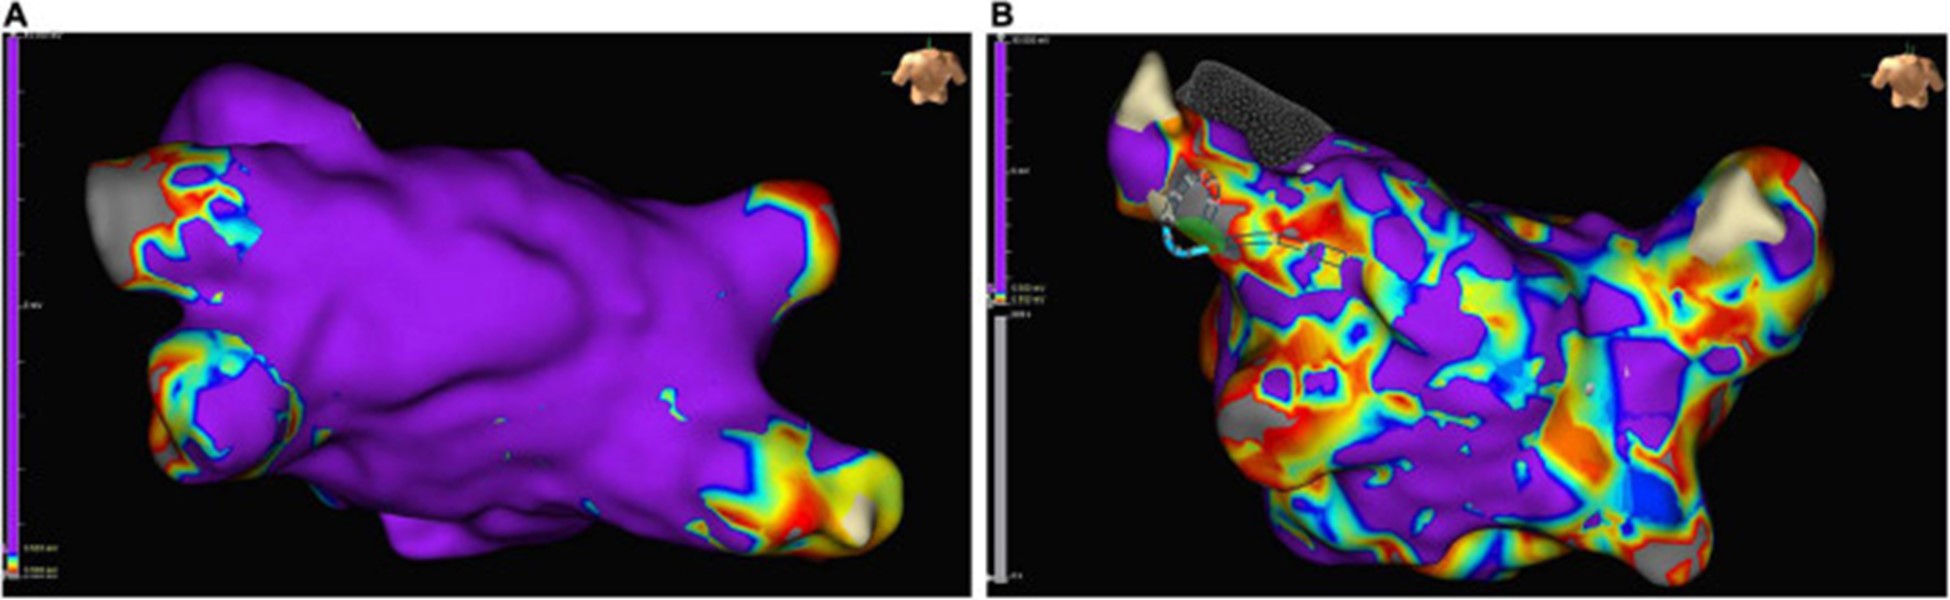

非局灶性 LA 心动过速患者在心内膜标测中出现高比例的低电压区域,为可能的左心房心肌病提供了证据 (图 6)。对纤维化左心房心肌病患者的分析显示,随着纤维化左心房心肌病的严重程度增加,严重的纤维化区域增加,贼大 LA 电压降低(101)。

图 6:在接受肺静脉隔离的窦性心律患者的左心房心内膜标测中的低电压区域示例:正常传导的心房心肌呈紫色,低电压区域(定义为电感知幅度≤0.5 mV的区域)是颜色不同。(A)几乎没有低电压区域的左心房示例。(B)低电压区域 > 10% 的严重疾病左心房示例。

大多数评估电解剖标测对评估左心房心肌病的益处的研究包括接受导管消融的 AF 患者。有强有力的证据表明,AF 患者同时具有更多的低电压区域和严重的纤维化区域,反映了心房的电和结构重塑 ( 100 – 110 ) (图 6)。